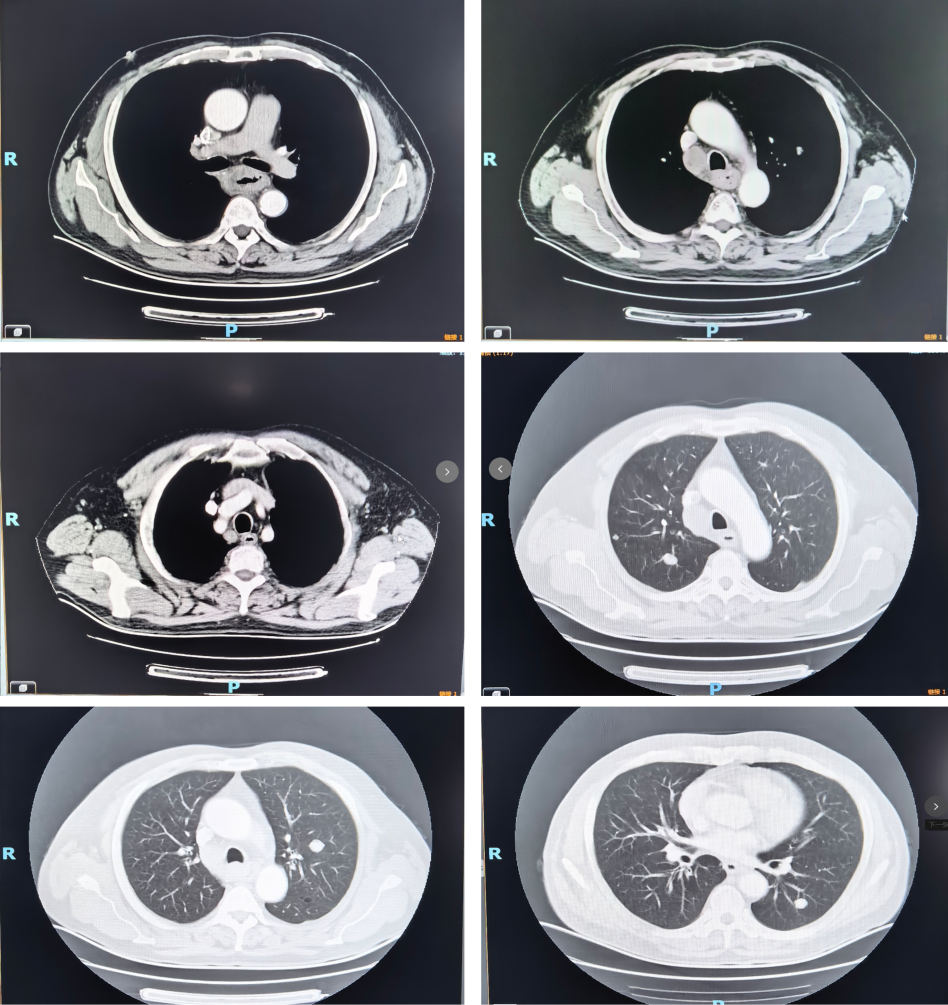

颈部+上腹部+胸部增强CT(2025年8月1日):食管占位,倾向恶性;纵隔淋巴结肿大,倾向转移;双肺多发结节,倾向转移可能。

1周期后(2025年9月)复查CT:食管病变、纵隔淋巴结较前减小,双肺转移结节较前部分减小。1周期即显现疗效。

4周期后(2025年11月)复查CT:与2025-10-17日图像对比,食管癌治疗后改变,同前相仿;纵隔淋巴结治疗后改变,较前减小;双肺多发小结节,考虑转移瘤治疗后改变,部分较前略减小。

疗效评估:达到部分缓解(PR)

本例患者PD-L1 CPS评分为3分,属于CheckMate 648研究中获益更为显著的PD-L1阳性人群。经过4个周期纳武利尤单抗联合化疗后,影像学复查显示原发灶及所有转移病灶均明显缩小,疗效评估达PR,与研究中PD-L1阳性患者高达53%的ORR相符。